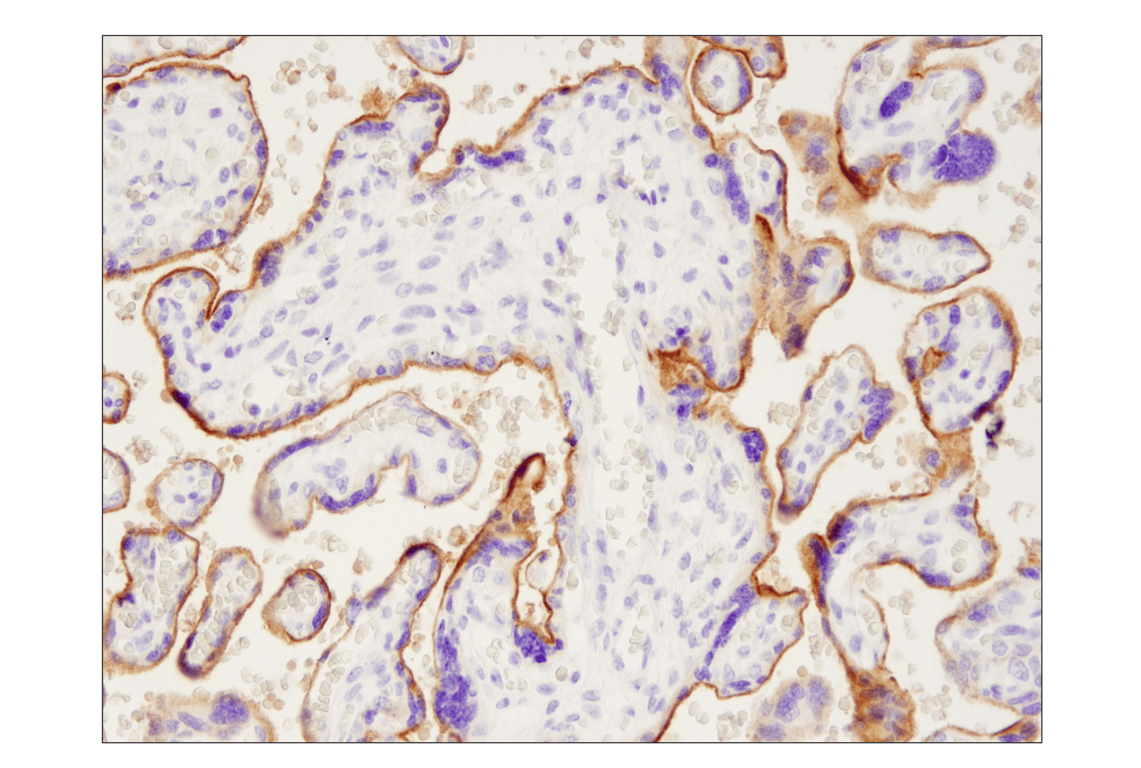

Immunohistochemical analysis of paraffin-embedded human placenta using PD-L1 (Extracellular Domain Specific) (E1J2J™) Rabbit mAb.

Immunohistochemistry Image 2: PD-L1 (Extracellular Domain Specific) (E1J2J<sup>™</sup>) Rabbit Monoclonal Antibody